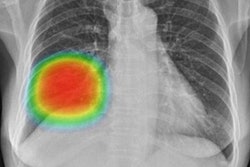

Under the terms of the deal with the Korean National IT Industry Promotion Agency, Lunit will deliver its Insight CXR software to more than 30 Korean military medical sites by the end of 2022. The software detects nine types of abnormalities via chest x-ray and aims to better detect critical lung diseases, including tuberculosis.